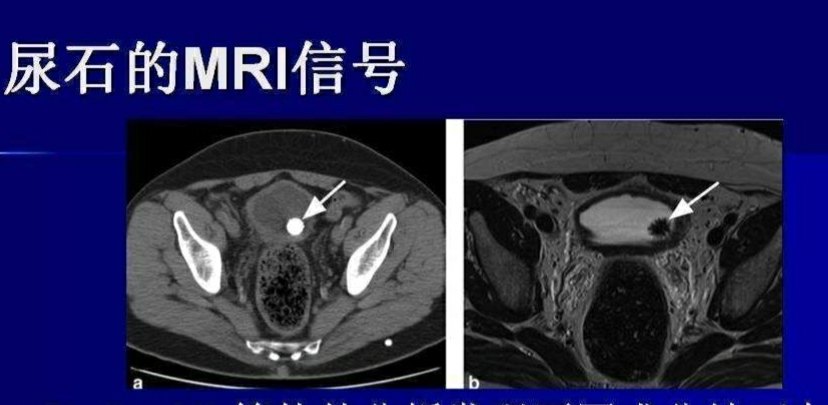

磁共振、

血、尿常规等检查确诊。